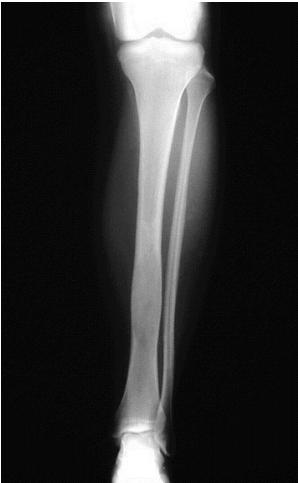

Diaphyseal Lesions: Detailed Examples

Common Diaphyseal Tumors

- Osteoid osteoma

- Fibrous dysplasia

- Osteofibrous dysplasia

- Adamantinoma

- Ewing’s sarcoma

Osteoid Osteoma

Thick cortex